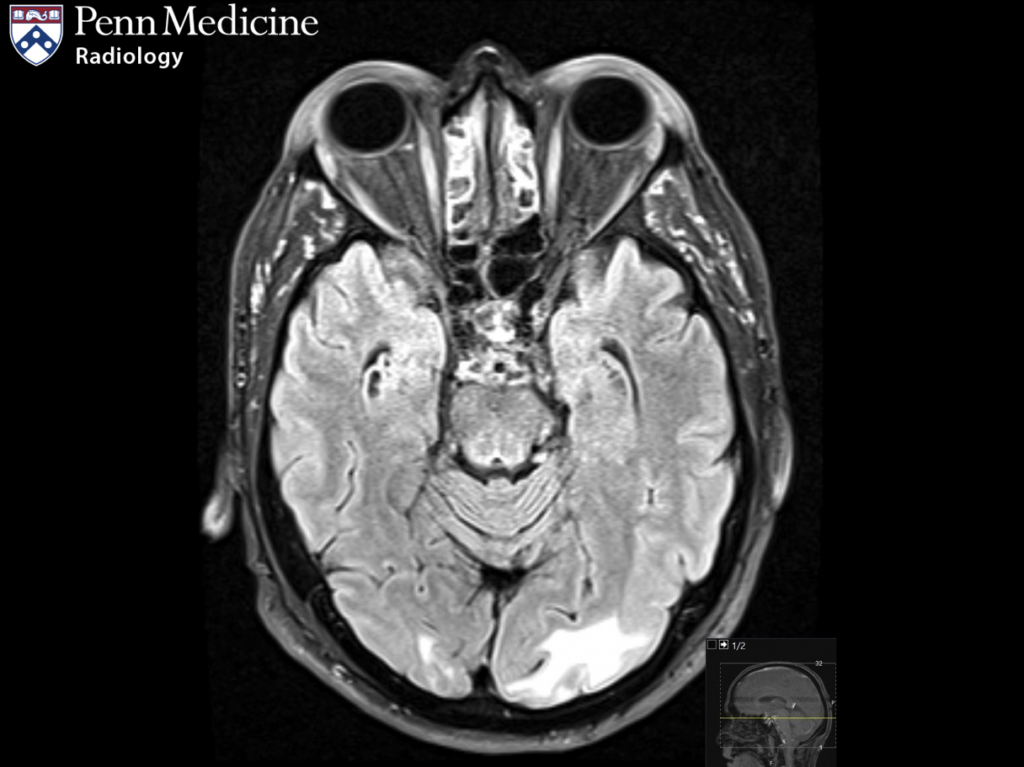

66-year-old woman with gradually worsening vision

A 66-year-old woman presented with gradually worsening vision.